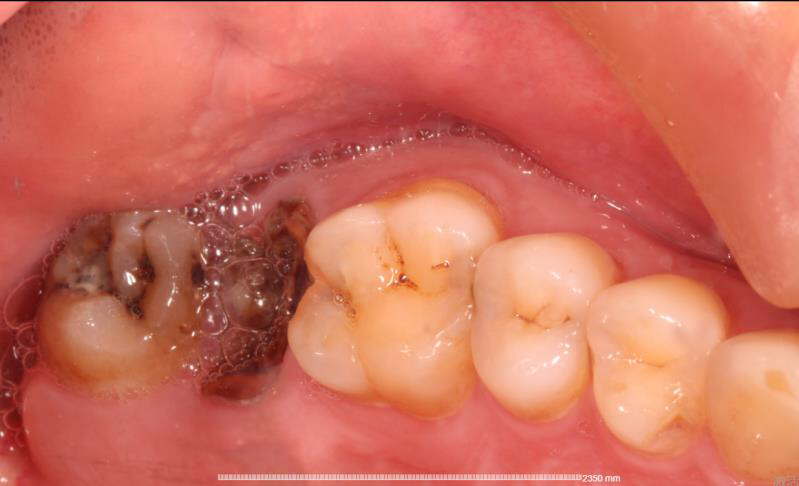

患者中年男性,右上5、6号牙邻接处龋坏,虽然表面没有明显龋坏,但釉质下可见低密度阴影,去龋过程中见釉质下大面积龋坏。由于龋坏面积较大,且位置处在邻接处,传统补牙强度较弱,所以我们建议这位患者采用嵌体修复的方式,一日就诊,一次搞定。

这种邻接龋坏多数是由于进食过后没有用牙线的习惯,食物嵌塞在2颗牙之间导致2颗牙都发生龋坏,卢医生建议大家要有进食过后使用牙线的习惯。